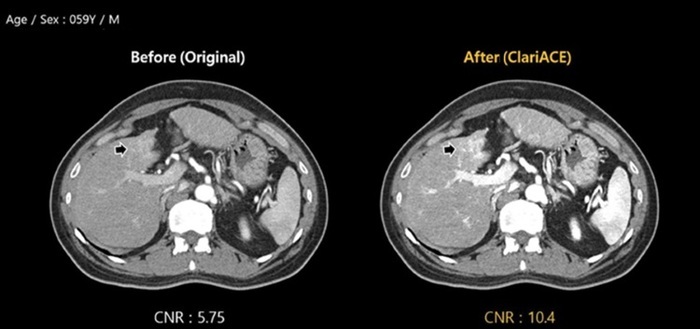

이를 위해 최근에는 ClariCT.AI에서 한층 진화한 'ClariACE'도 최근 선보였다. 이 제품은 CT 조영제 부작용을 최소화 할 수 있는 AI 기반의 조영증강기술 솔루션이다.

설명: 간암 CT 검사서 클라리파이 AI 기반 조영증강기술 솔루션 ClariACE CT 적용 사진. 화살표 방향의 간 종양이 원본에서는 조영제 도달 부족으로 희미한데 반해 ClariACE에서는 더욱 뚜렷해졌다.

여기에 AI 조영증강기술은 조영제를 투여하는 CT 검사에서 혈관이나 종양 등 관찰부위의 조영제 도달 부족으로 이미지 대조도가 낮아 진단이 어려울 경우, 재검사의 필요 없이 기존 CT 영상에서 AI 기술만으로 조영제를 더 주사한 것과 같은 증폭효과를 낸다.

클라리파이 박재우 영업팀 부장은 "CT를 찍기 전 투여하는 조영제 용량을 약 30~60% 줄여줄 수 있다"며 "방사능에 적게 노출되면서도 조영제 부작용까지 줄여주는 ClariCT.AI의 상위 버전"이라고 설명했다.